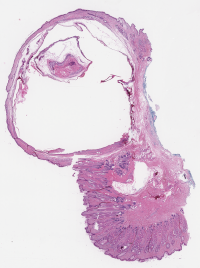

Category Train Validation Image Example

(Count) 1271 317 [Uncaptioned image]

(No-Count) Lipomas 703 176 [Uncaptioned image]

(No-Count) Non-neoplastic lesions 400 100 [Uncaptioned image]

(No-Count) Skin punch biopsies 180 45 [Uncaptioned image]

(No-Count) Skin&subcutaneous tissues 522 131 [Uncaptioned image]

Table 1: Biopsy slide classification data